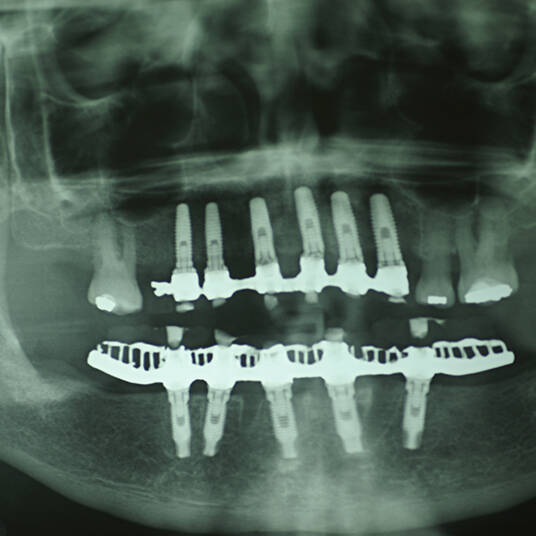

- Planejamento Digital: Com o auxílio de tecnologias como tomografias e softwares 3D, a posição dos implantes é planejada com precisão.

- Cirurgia de Instalação dos Implantes: Os implantes são fixados no osso maxilar ou mandibular, proporcionando uma base sólida para a prótese.

- Fixação da Prótese: Em até 72 horas após a cirurgia, a prótese provisória é instalada, permitindo que o paciente recupere a funcionalidade e a estética imediatamente.